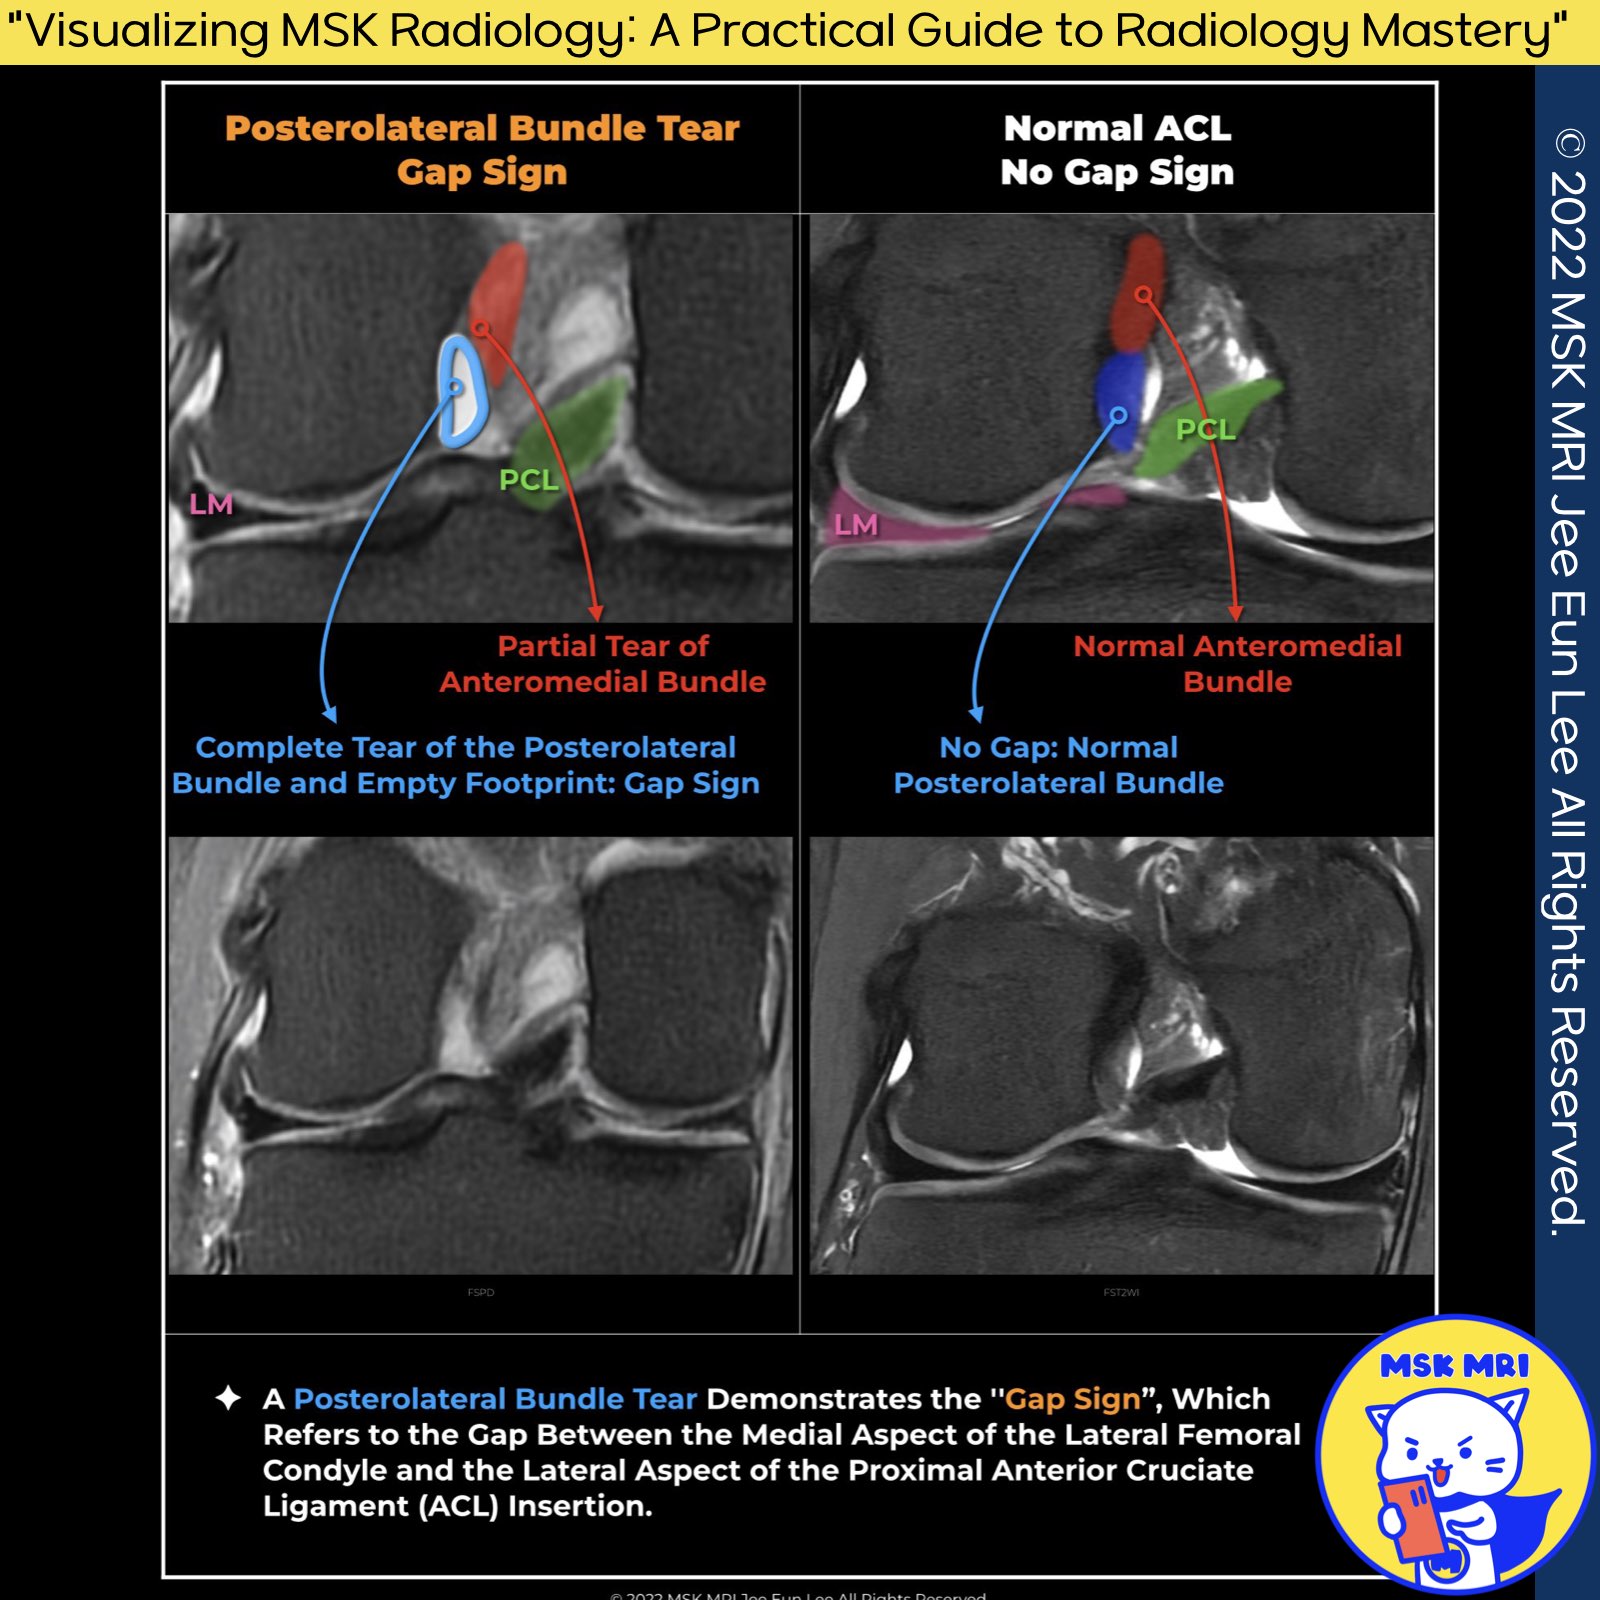

✅Imaging Signs of Isolated Posterolateral Bundle Tear of the ACL

An ACL tear may only involve one bundle. The specific imaging signs of an isolated posterolateral bundle tear include:

1️⃣Gap Sign

- Description: Presence of fluid signal and/or a gap.

- Location: Between the medial aspect of the lateral femoral condyle and the lateral aspect of the mid-ACL.

- Imaging Modalities: Can be seen on either axial or coronal MRI images.